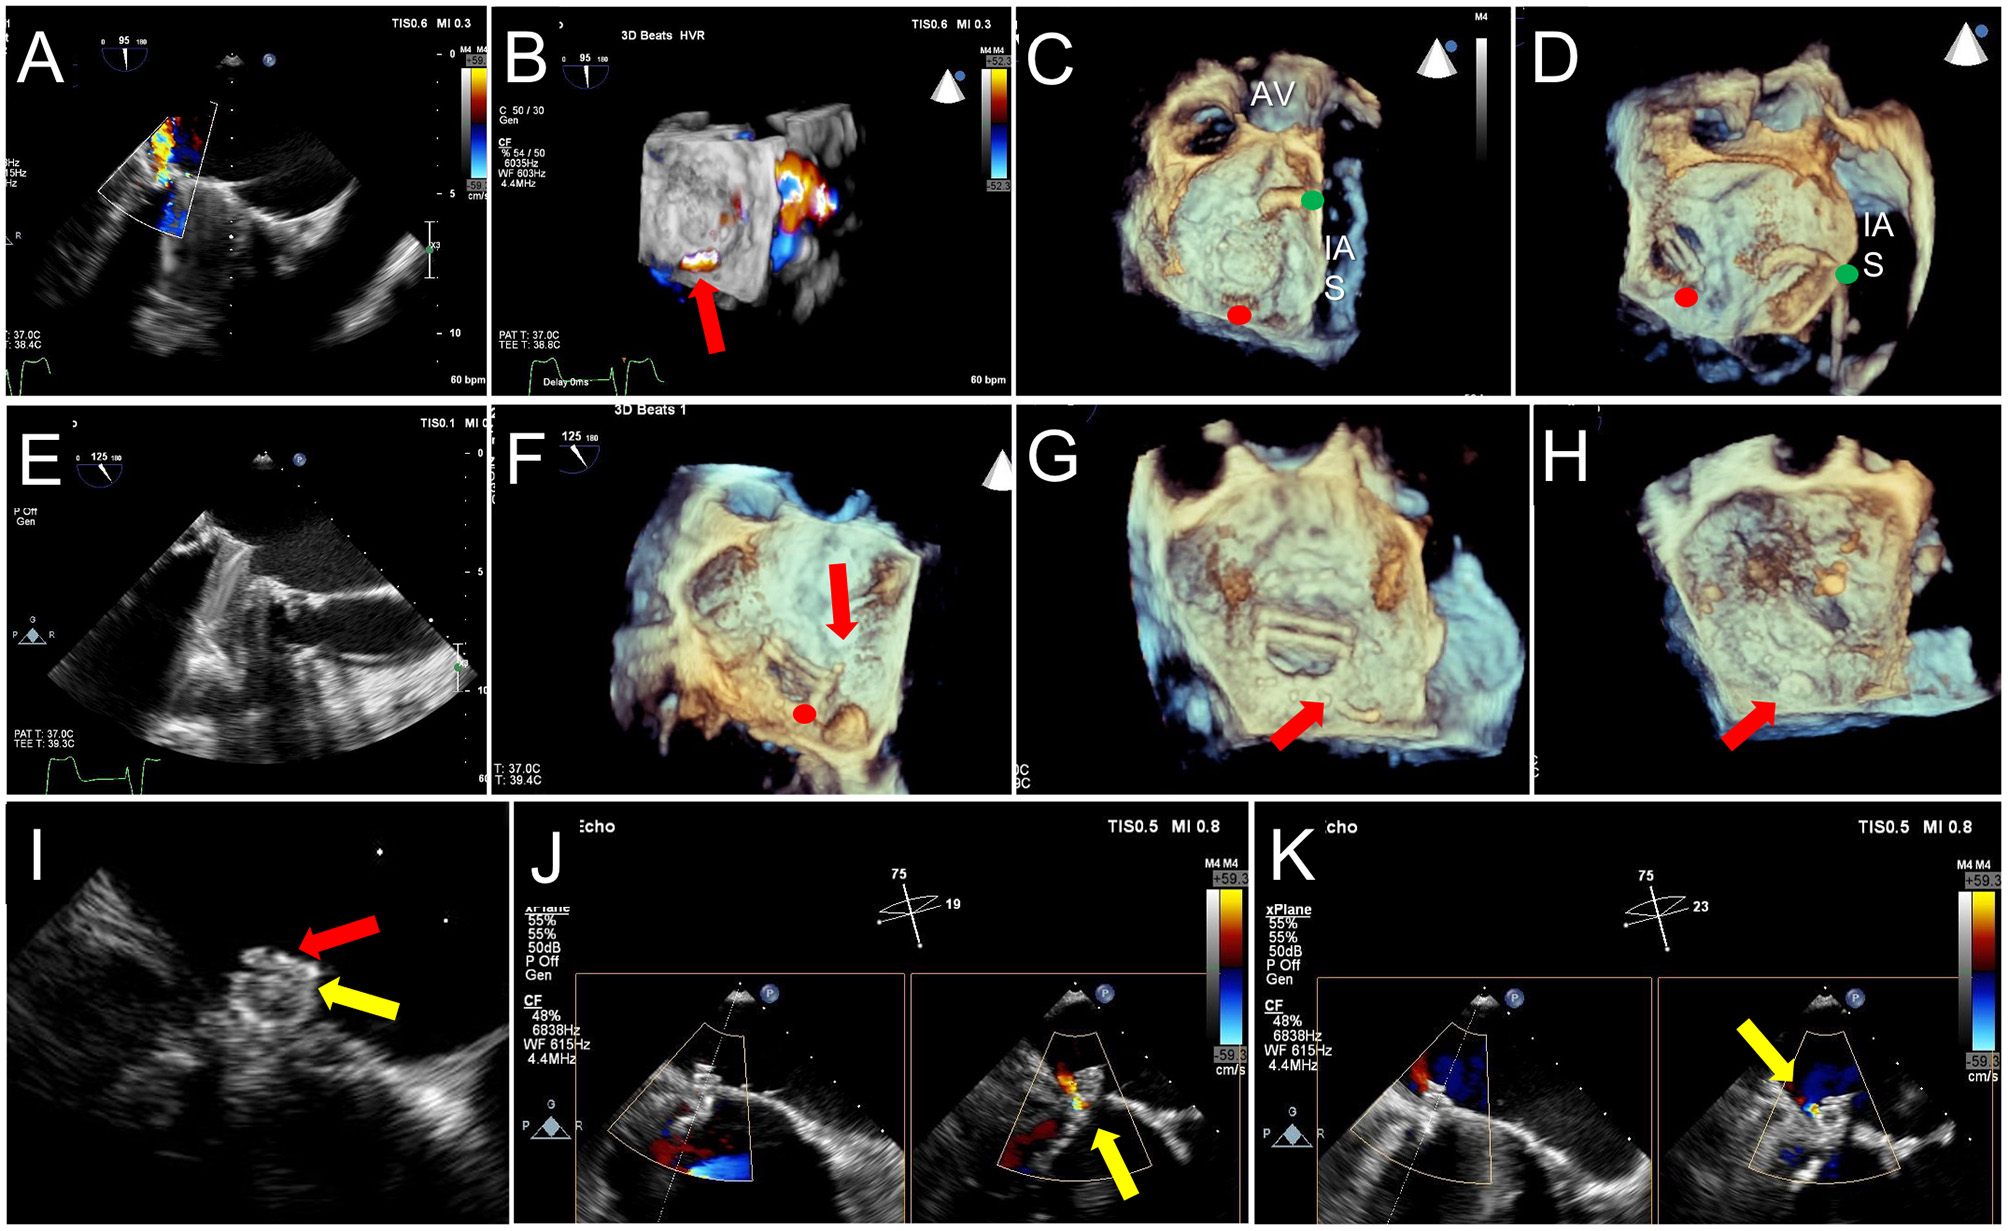

Figure 11

TEE Guidance of Challenging Closure of Posteromedial PVL. A posterior paravalvular leak resulting in hemolysis is visualized by 2D color Doppler (A) and 3D color Doppler Imaging (between 5 and 6 o clock in a surgeon's view, red arrow, B). (C) The first attempt at transseptal puncture is shown (green circle). The location of PVL is marked by a red circle. (D) After unsuccessful attempts to cross the defect, the septum was repunctured more posterior (green circle) for a better trajectory toward the defect. (E) After additional unsuccessful attempts, the approach was changed to retrograde. (F) As acoustic shadowing limits visualization on the ventricular aspect of the mechanical mitral prosthesis, wire exit point was visualized in the left atrium. Here, the wire is visualized inside the sewing ring (red arrow) adjacent to the PVL (red circle). (G) After reorientation of the wire, the defect was successfully crossed (red arrow). (H) The atrial disk of an AVPII closure device is visualized after deployment on 3D imaging (red arrow). (I) 2D echocardiography demonstrates the atrial disk (red arrow) and a portion of the center cylinder (yellow arrow). (J) A residual peri-device jet is seen (yellow arrow). (K) After device re-sheathing and slight repositioning, there is a trivial residual PVL jet flowing through the center of the closure device (yellow arrow). AV, aortic valve; IAS, interatrial septum.